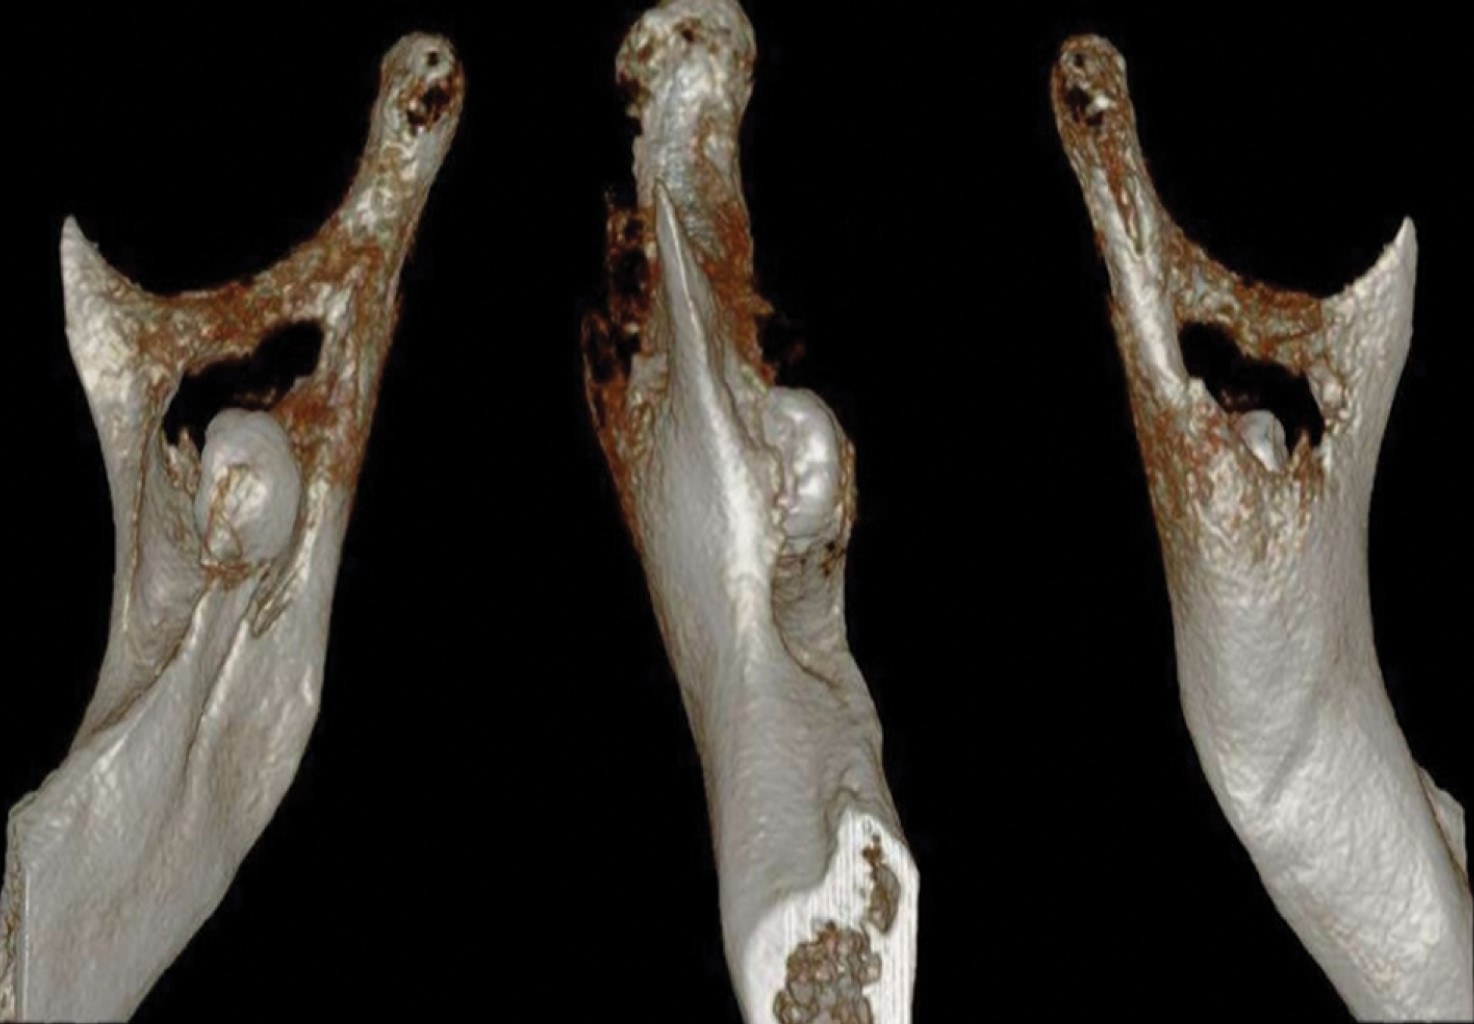

Heterotopic third molars are teeth that are embedded in the maxilla and mandible, remote from their usual eruption site. Its etiology is not well defined and there are various theories at the moment. These teeth can appear in different areas of the bone's structures, having a predilection for the jaw. They usually appear between the second and seventh decade of life, and in most cases are imaging findings. The mandibular third molar is the tooth with the most frequent heterotopia, being its usual location in the mandibular branch and in the subcondylar region. The dentigerous cyst is the most common associated pathology. We present a case of a long evolution heterotopic third molar in the right mandibular branch, related to a dentigerous cyst which was managed under local anesthesia. The etiology, surgical technique and special considerations related to heterotopic teeth are described.

Figure 1